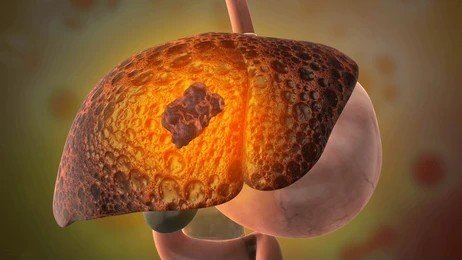

Liver transplant is a complex but life-saving procedure for patients with severe liver disease, liver failure, or certain liver cancers. It involves replacing a diseased liver with a healthy one from a living or deceased donor. At our Liver Transplant and HPB Surgery Care center, we provide comprehensive care for both adults and children, ensuring safety, precision, and excellent outcomes.